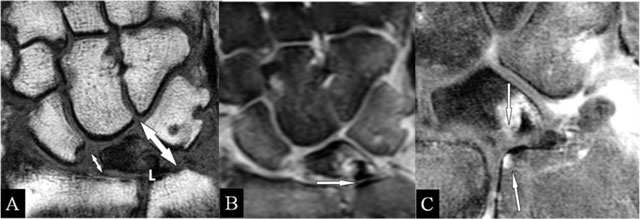

Figure 7

Lunar abutment. (A) Coronal SE T1-WI; (B) Coronal SE PD-WI FS; and (C) Coronal SE T1-WI FS with gadolinium. (A) Due to loss of height at the radial side, the ulnar side of the lunate bone (L) approaches the ulnar head. (B) Sclerotic borders at the contact zones (arrow), oedema at the ulnar corner of the lunate bone and TFCC tear. (C) Contrast enhancement in the zones of the kissing marrow oedema.